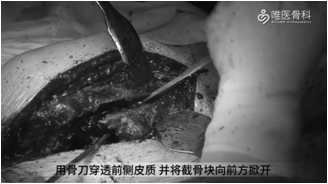

②用摆锯按照截骨线锯开股骨后方皮质,在预定平面横向分离侧方皮质。用骨刀穿透前侧皮质,并将截骨块向前方掀开,直视下清除残留骨水泥。